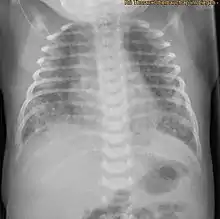

X-ray showing the extent of lung epithelial damage in response to meconium seen in neonates with meconium aspiration syndrome. | |

Apoptosis is an important mechanism in the clearance of injured cells and in tissue repair, however too much apoptosis may cause harm, such as acute lung injury. Meconium induces apoptosis and DNA cleavage of lung airway epithelial cells, this is detected by the presence of fragmented DNA within the airways and in alveolar epithelial nuclei. Meconium induces an inflammatory reaction within the lungs as there is an increase of autophagocytic cells and levels of caspase 3 after exposure. After 8 hours of meconium exposure, in rabbit foetuses, the total amount of apoptotic cells is 54%.[15] Therefore, the majority of meconium-induced lung damage may be due to the apoptosis of lung epithelium.[1]